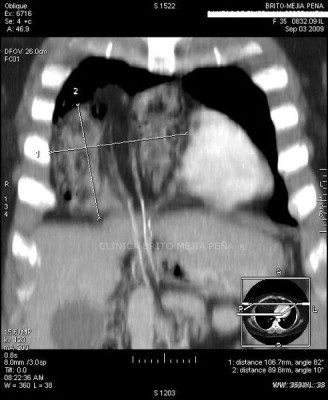

Hernia morgagni coronal